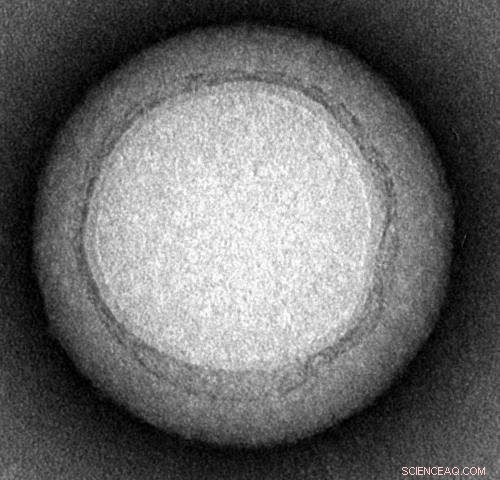

Engineers at the University of California, San Diego have invented a "nanosponge" capable of safely removing a broad class of dangerous toxins from the bloodstream, including toxins produced by MRSA, E. Coli, poisonous snakes and bees. The nanosponges are made of a biocompatible polymer core wrapped in a natural red blood cell membrane. Credit: Zhang Research Lab

Transmission electron microscopy demonstrated that the nanosponges are approximately 85 nanometers in diameter. Credit: Zhang Research Lab, UC San Diego Jacobs School of Engineering

Each nanosponge has a diameter of approximately 85 nanometers and is made of a biocompatible polymer core wrapped in segments of red blood cells membranes.